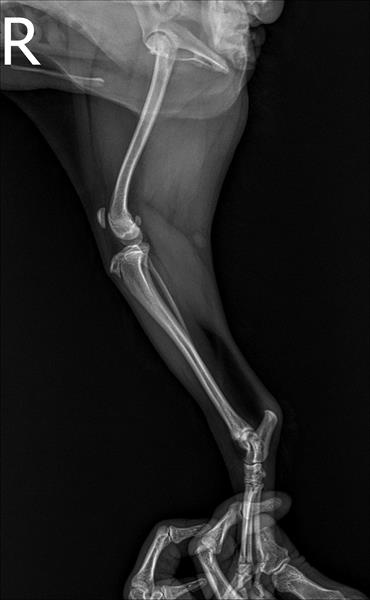

엑스레이 사진으로만 봤을 때, 슬개골 탈구 4기와 대퇴골·경골의 각변형이 보입니다.

각변형은 쉽게 말해 다리 축이 틀어진 것인데, 이 구조에서는 슬개골이 제자리에 있기가 힘듭니다.

이런 경우 슬개골만 수술한다면 잠깐 좋아질 수 있어도, 다시 탈구될 가능성이 높습니다.

각기 수술은 뼈를 정상 축으로 바로잡아 슬개골이 빠질 이유 자체를 없애는 수술이라, 우리 아이의 경우 과하지 않고 오히려 정석에 가까운 선택일 수 있습니다.